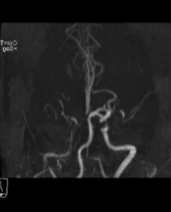

神经介入诊疗中心主任、副主任医师刘俊中接诊后,根据各项检查检验结果迅速判断张女士属于颅内大血管病变。

左侧大脑中动脉和颈内动脉均已闭塞,相当于左侧大脑半球几乎断了供血,手术指征明确。

5 分钟后,张女士被推进介入手术室,急诊脑血管造影进一步确认了血管闭塞情况。

10 分钟后,手术顺利完成,堵塞血管成功开通,濒临坏死的脑细胞被及时 “救回”,张女士的病情得到了有效控制。